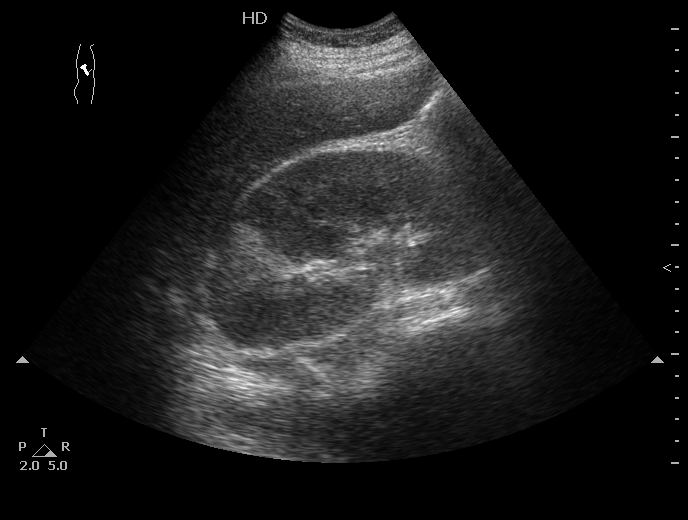

Через три дня

Острый правосторонний апостематозный пиелонефрит, формирующиеся абсцессы почки. МКБ, конкремент правой почки.

Пациентка переведена в урологию, где ей проводится консервативное лечение.

Как выглядят собственно апостемы я показать не смогу, так как у меня нет такого замечательного высокочастотного датчика как у вас в детской больнице (вспоминаю сонограммы почек при поликистозной болезни новорожденных здесь на форуме). А вот как выглядит почка с таким заболеванием - см пост 1.

Это - большая почка со сравнительно маленьким центральным эхокомплексом, неравномерно гипоэхогенной паренхимой и отсутствием кортикомедуллярного контраста.